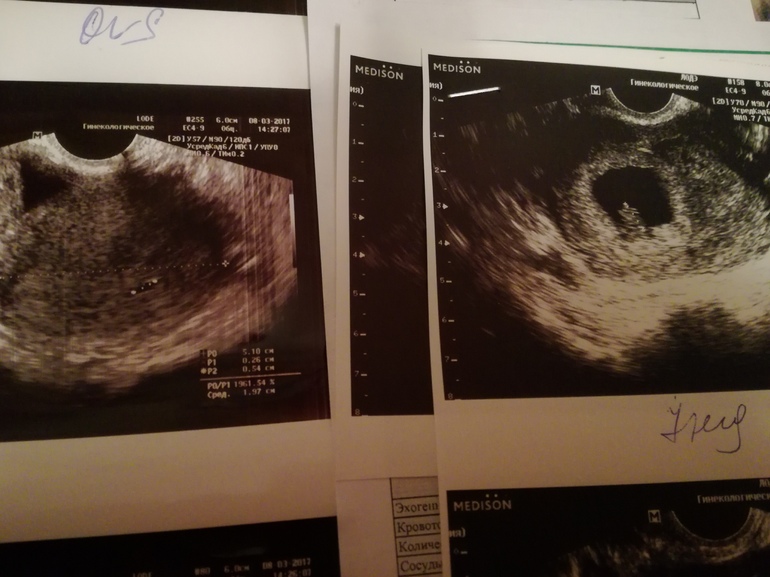

Марабэ 9 лет Узи Два узи, первое 8 марта, второе 23 марта Посмотрите еще 20 записей на эту тему Отменить Ответить Мария Мои поздравления! Растите здоровенькими) уже скоро будет плановое узи в 12 недель и там будет уже полноценный человек! Я тоже из Минска, поэтому обращайся если что 05.04.2017 Ответить Марабэ Спасибо! 05.04.2017 Ответить Символы, мысли, энергия Третье узи Чаты Беременных Выберите чат: Январята-2026 Февралята-2026 Мартята-2026 Апрелята-2026 Майчата-2026 Июнята-2026 Июлята-2026 Августята-2026